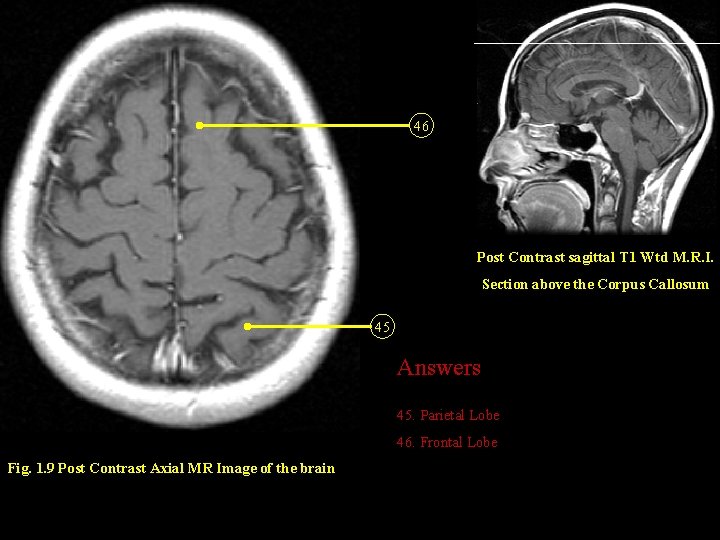

46 Post Contrast sagittal T 1 Wtd M. R. I. Section above the Corpus Callosum 45 Answers 45. Parietal Lobe 46. Frontal Lobe Fig. 1. 9 Post Contrast Axial MR Image of the brain